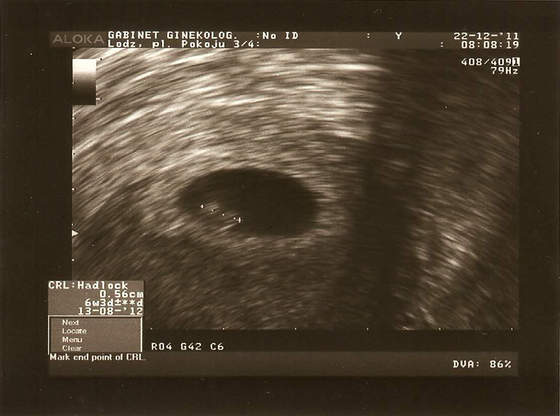

Zupełnie mnie to ujęcie rozczula...!Błonka a dlaczego za okrągłe? Mój mały też ma taki zgrabny, okrąglutki pęcherzyk żółtkowy na podorędziu:-)